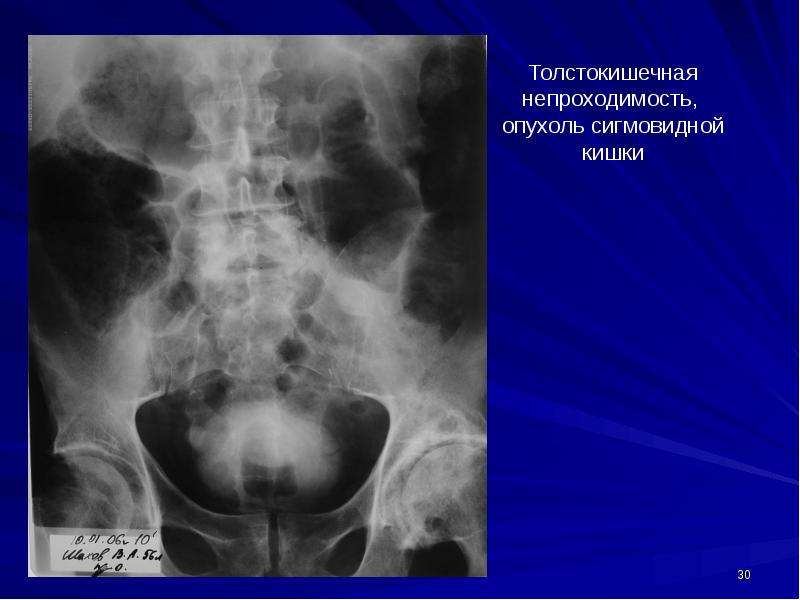

Иллюстрации и информация о симптомах острого кишечного непроходимости